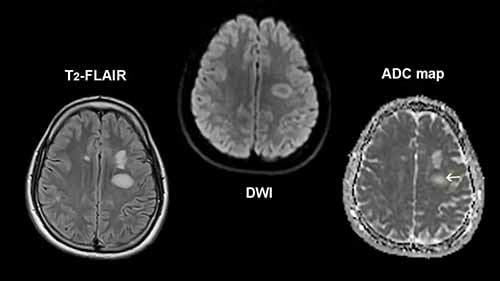

类别:医学影像技术

简介:作为美国第三方影像诊断中心的行业龙头,RadNet是否具有投资价值?莎伦和托德就这个问题进行了探讨。